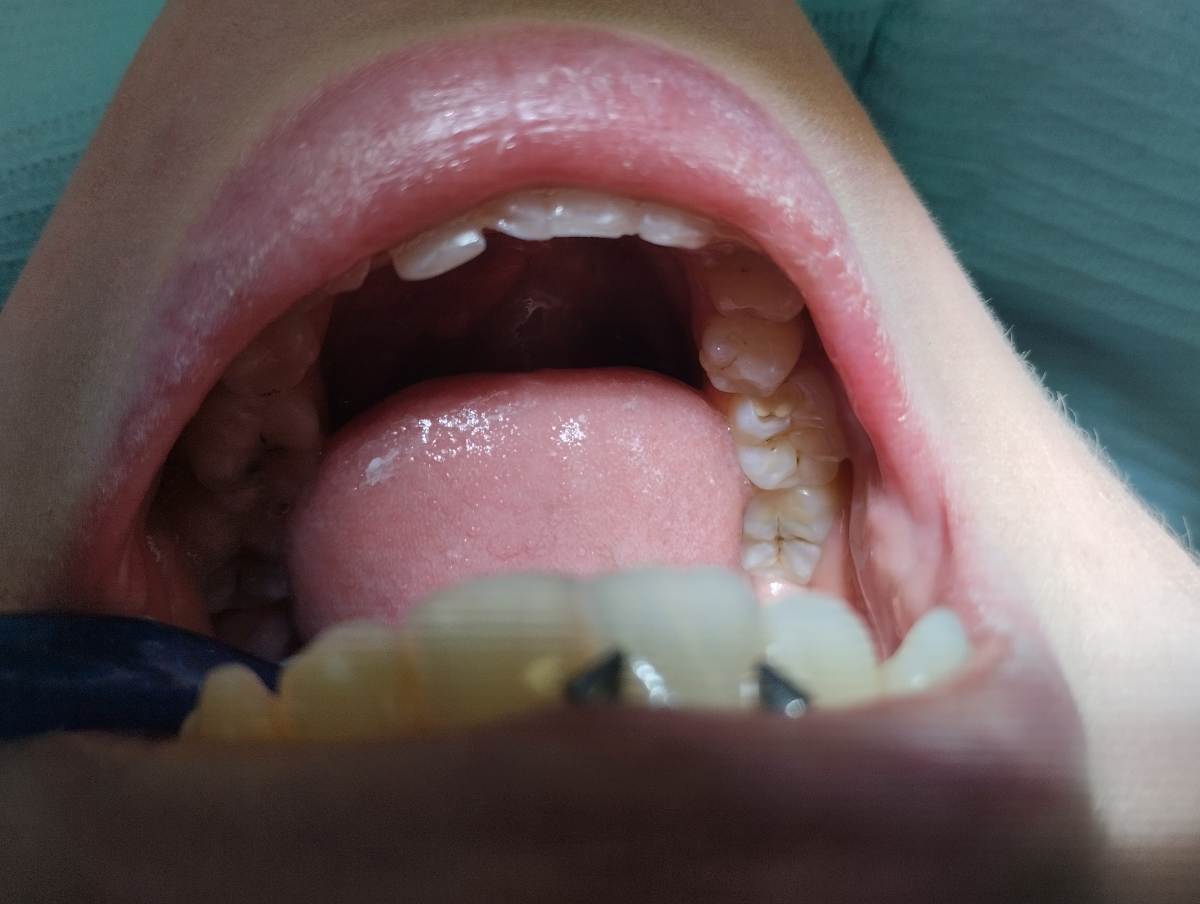

Александр1 Опубликовано 29 апреля Поделиться Опубликовано 29 апреля Здравствуйте, я молодой стоматолог. Ко мне приходил пациент на лечение кариеса дентина зуба 4.6(средний), 1 класс по Блэку. На следующий день после лечения появилась боль при накусывании на пломбу, пациент пришёл ко мне через 3 недели, что боль не прошла, я проверил на суперконтакт, его не обнаружилась, предположил дебондинг, заменил полностью пломбу, 5 дней все было хорошо, но потом опять появилась такая же боль, в этом месте(в углу пломбы). Реакции на холод и тепло нет, других каких-то симптомов тоже нет, был совсем не глубокий средний кариес. Помогите пожалуйста🙏🙏🙏, что мне делать Ссылка на комментарий

Александр1 Опубликовано 29 апреля Автор Поделиться Опубликовано 29 апреля (изменено) Извините, только такие(до и после) Изменено 29 апреля пользователем Александр1 Ссылка на комментарий

Александр1 Опубликовано 30 апреля Автор Поделиться Опубликовано 30 апреля В этой точке, пациент говорит в самом углу, боль ощущается при зондировании пломбы, сами ткани зуба безболезненны Ссылка на комментарий